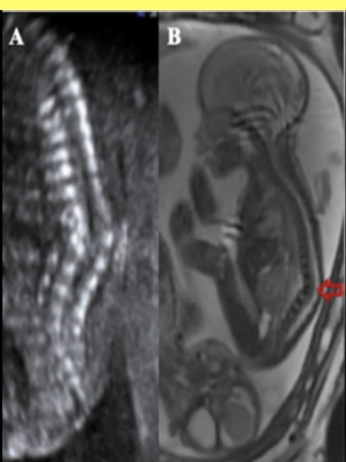

the cerebellum shows what sono sign

a) fruit salad

b) banana sign

c) lemon sign

d) string of pearls sign